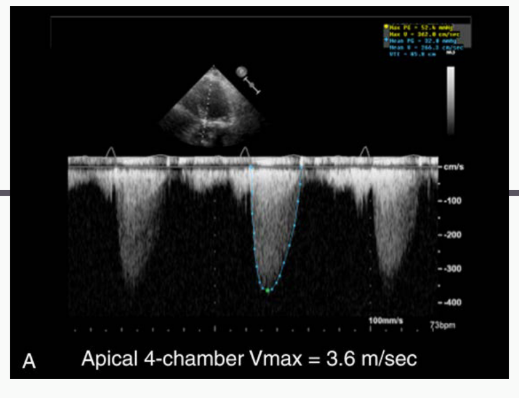

PEAK AORTIC FLOW VELOCITY ASSESSMENT

what does this measure, and how is this measured?

Antegrade systolic

velocity across the AV

⢠HIGHEST CW Doppler

jet

PEAK AORTIC

FLOW VELOCITY

B e s t V i ew s : A p i c a l 3 o r 5 C h am b e r,

Right Sternal Border, right

c l a v i c ul a r, and Suparsternal Notch